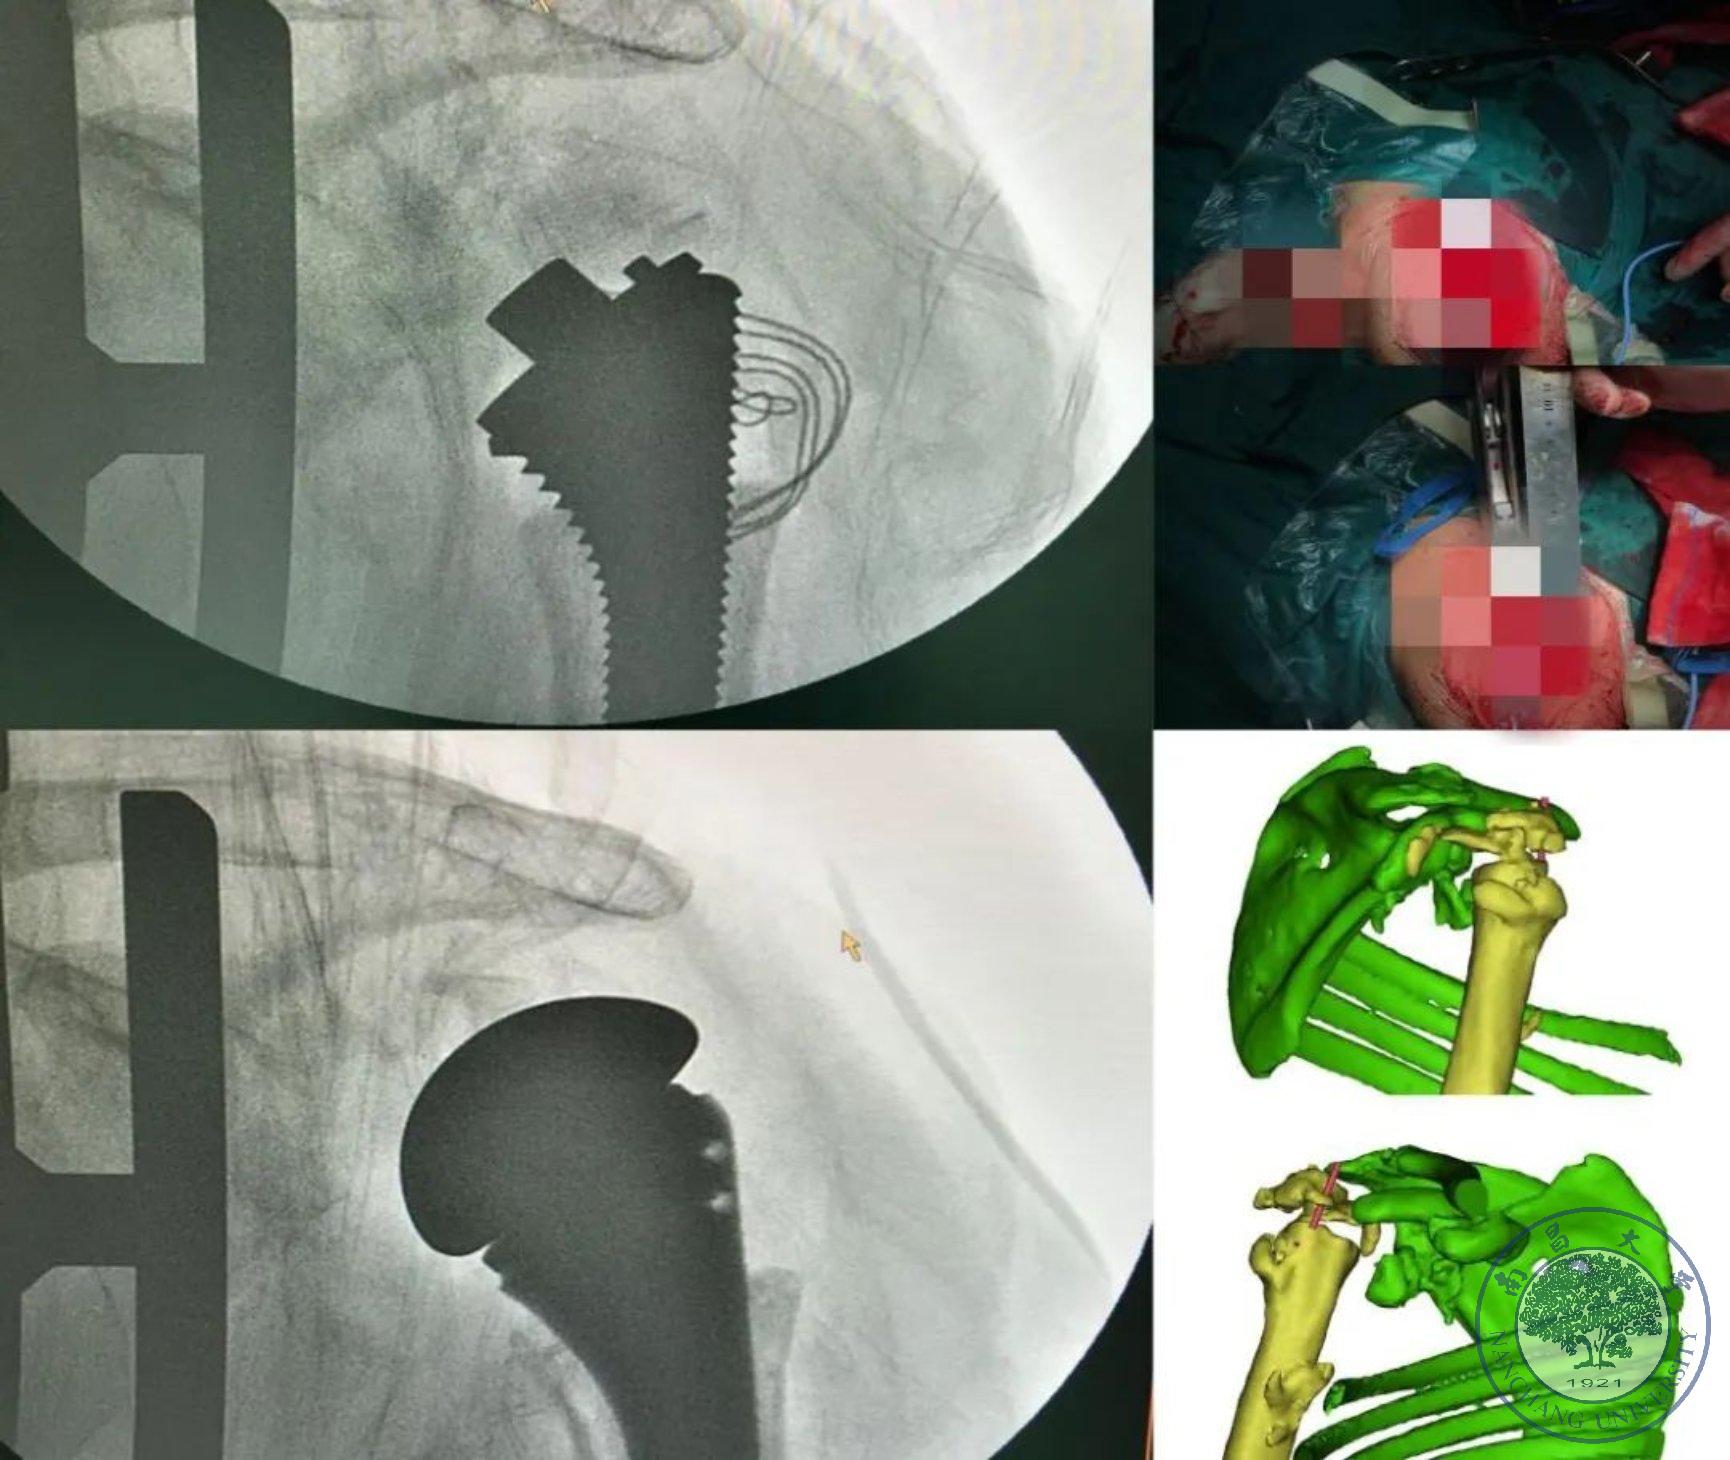

因患者右侧肱骨头已经完全溶解,肩关节处于完全脱位状态,无任何参照标志来提供肱骨近端假体植入深浅及旋转等重要参数,而无法精确进行肱骨头置换手术。患者入院后,在于雪峰教授主持下,由邓高荣主任主导组织病情讨论后,最终选择采集CT影像数据进行3D建模技术重建对侧(左侧)肱骨头3D模型,经过镜像处理后作为参照物,为患侧进行肱骨头置换手术。常规技术对该特殊患者无法精确定位,完全依靠术者经验安置假体,在该技术辅助下使得术中定位准确,假体安置科学精准,有效缩短手术时间,术后肢体长度及肩关节松紧度均恢复到健康时状态,达到更好的手术效果。在与患者及家属充分沟通后,术前准备充分后,由邓高荣主任、涂远青医生、姜浪医生团队在麻醉科及手术室全力配合下,成功为患者实施了数字化骨科3D建模技术辅助下的右肩肱骨头置换术,术中出血少,手术时间短,最大程度的使患者的肩关节功能得到恢复,患者及家属对术后效果恢复满意。 此次骨科利用数字化骨科3D建模技术辅助治疗右肩夏科氏关节,为患者成功完成右侧肱骨头置换术,是数字化骨科及其相关技术在骨科临床应用中的又一次“啃硬骨头”的尝试,为临床医师在面对复杂病例时提供了科学精准的数字化指导,使我院在人工关节置换手术技术层面又迈进了坚实的一步。

3D建模及打印技术是20世纪80年代出现的重要技术,近30年来发展迅速,现在在骨科的应用已经非常成熟,形成数字化骨科。对于骨折患者,尤其是复杂骨折患者,术前有实体解剖模型用于分析或模拟手术操作较单纯依靠二维平面的MRI或CT扫面更具指导意义,临床结果表明使用3D模型组较非3D模型组手术时间更短、术中出血量及术后引流量更少,有利于骨折的精确复位,提高手术精度、缩短手术时间、达到更好的手术效果。